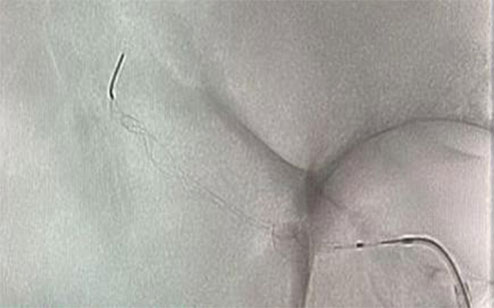

Adecuado para eliminar coágulos de sangre de los vasos sanguíneos y reconstruir la circulación sanguínea.

Al extraer el trombo la malla cambia para capturar, sujetar y extraer el trombo.

El diseño exclusivo de celdas variadas tiene una captura más eficiente al sujetar los coágulos después de la integración.